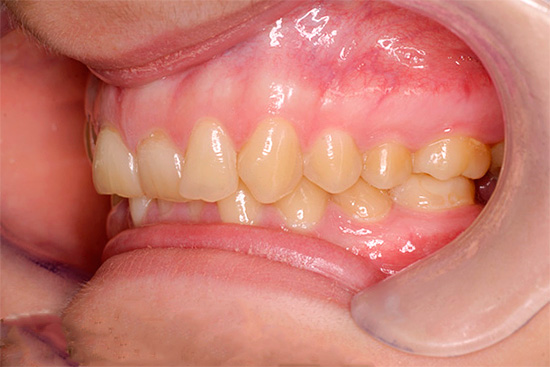

La fotografia sotto mostra un esempio di morso incrociato in un adulto:

Reclami frequenti da pazienti e genitori:

- la presenza di un difetto estetico con una notevole discrepanza tra dimensione e posizione delle mascelle;

- difficoltà a mangiare;

- violazione della pronuncia del suono;

- malattia gengivale dovuta a possibili lesioni durante la masticazione e la parola;

- problemi al tratto gastrointestinale.